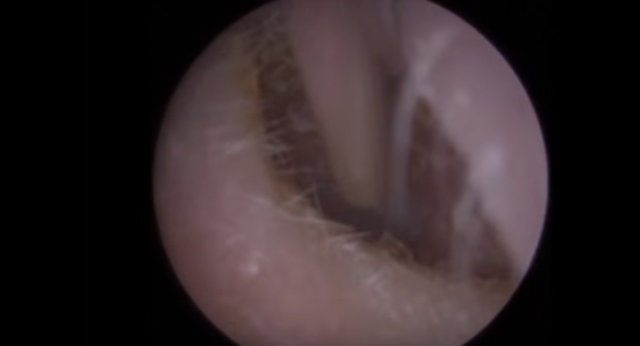

Kulağından 22 tane nesne çıkarılan adam hayrete düşürdü. İşin garip yanı ise kulağının içinden çıkan şeylerin işitme cihazı olmasıydı...